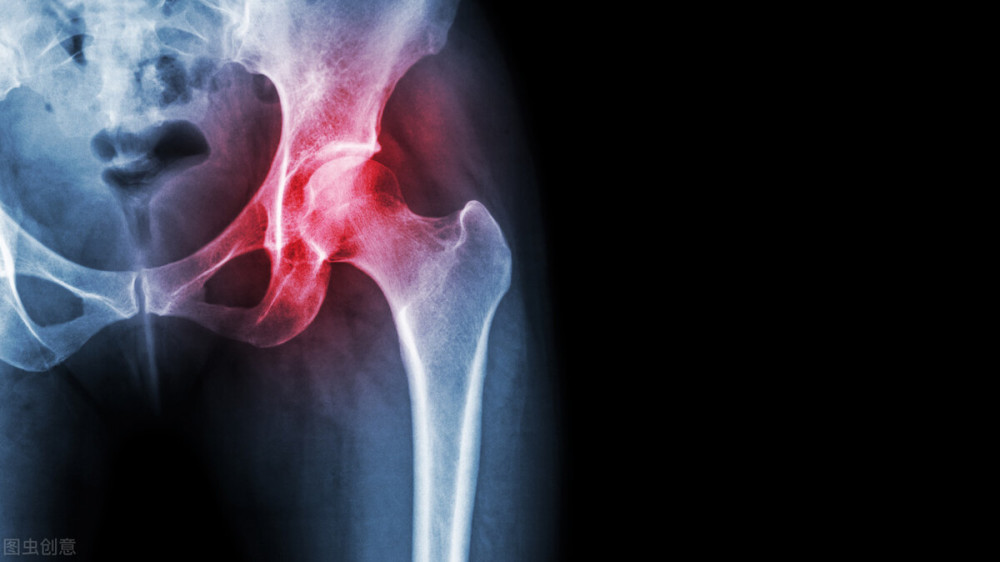

股骨头为什么会坏死呢?早期的股骨头坏死怎么治疗?

股骨头为什么会坏死呢?

股骨头坏死的发病机制比较复杂,有很多原因导致股骨头坏死,其中主要的三个原因:

1.外伤:外伤以后导致股骨头坏死很重要的一个原因就是把供应股骨头血液和营养的血管破坏了。

2.激素:有些患者因为风湿类疾病或者肾脏疾病不得不应用激素治疗,而过量使用激素会影响血管内的血流,间接影响股骨头的血供,最终导致股骨头坏死。

3.酒精:过量饮酒会引起血液凝固状态的改变,血凝块如果堵塞股骨头供血的血管,就会导致股骨头缺血坏死。

股骨头坏死有哪些症状?

患上股骨头坏死后,患者主要的症状有臀部、腹股沟酸疼、髋关节疼痛,

在负重或者运动后这种症状会明显加重,如不妥善治疗的话,可导致髋关节功能障碍甚至终身残疾。